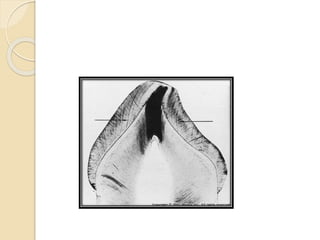

PRIMARY DENTIN

Caused :by a mild stimulus as slowly progressing

caries, mild attrition or abrasion or as normal age

change.

Mechanism: mild stimulus will lead to mild injury

which lead to fatty degeneration and calcification

of entire D.T in affected area or in old aged dentin

due to continued deposition of calcium ions which

lead to complete closure of D.T this will prevent

stimulus from extend toward pulp make pulp less

sensitive.

Histologically: in G.S appear as transparent in

transmitted light and black under reflected light.

Both dead tract and sclerotic dentin are age

change occur in primary dentin.

- Caused by sever stimuli as rapid progressing

caries. Where is no time to form reparative

dentin. Or in area of narrow pulp horn due to

crowding of odontoblast.

- Odontoblastic process and

cell undergo total destruction & D.T

appear empty filled with air, so

appear black under transmitted light

and light in reflected light.